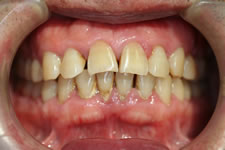

4. 中等度歯周炎

歯周ポケットが3~6mm以内、歯の揺れる幅が1~2mm以内で骨が半分程度溶けてしまった状態です。歯がぐらぐらし始め、歯ぐきは後退して歯が長くなったように見えてきます。

麻酔をして、SRP(スケーリング、ルートプレーニング)によって、歯の根の表面に付着したプラーク、歯石を取り除きます。

▼歯磨き指導で症状が安定しました。

治療前

治療後

▼SRP(スケーリング・ルートプレーニング)で症状が改善・安定しました。